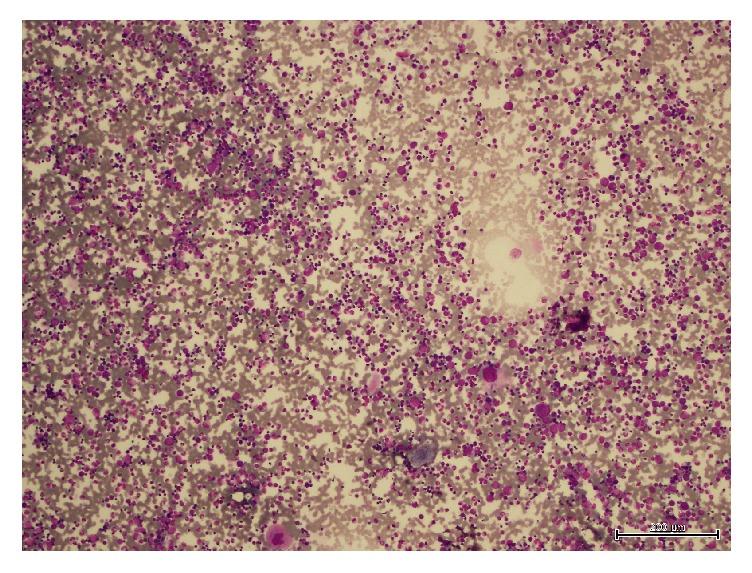

Thrombocytopenia is a frequent finding in patients with solid tumors. It is usually caused by bone marrow infiltration or by myelosuppression due to anticancer therapy; however immune thrombocytopenia (ITP) associated with solid tumors is rare. Neuroblastoma is the most common extracranial solid tumor in children. Here we report the case of a two-year-nine-month-old patient with adrenal neuroblastoma who presented with ITP. Paraneoplastic ITP was considered in the differential diagnosis. Bone marrow infiltration and other causes of thrombocytopenia were excluded and the patient was treated with intravenous immunoglobulin and tumor resection. Platelet count increased rapidly after surgery and complete remission of ITP was achieved.

血小板减少症在实体瘤患者中很常见。它通常由骨髓浸润或抗癌治疗引起的骨髓抑制所致;然而,与实体瘤相关的免疫性血小板减少症(ITP)却很罕见。神经母细胞瘤是儿童最常见的颅外实体瘤。在此,我们报告一例两岁九个月大的肾上腺神经母细胞瘤患者出现ITP的病例。副肿瘤性ITP被列入鉴别诊断。排除了骨髓浸润和其他血小板减少的原因,患者接受了静脉注射免疫球蛋白和肿瘤切除术治疗。术后血小板计数迅速上升,ITP实现完全缓解。